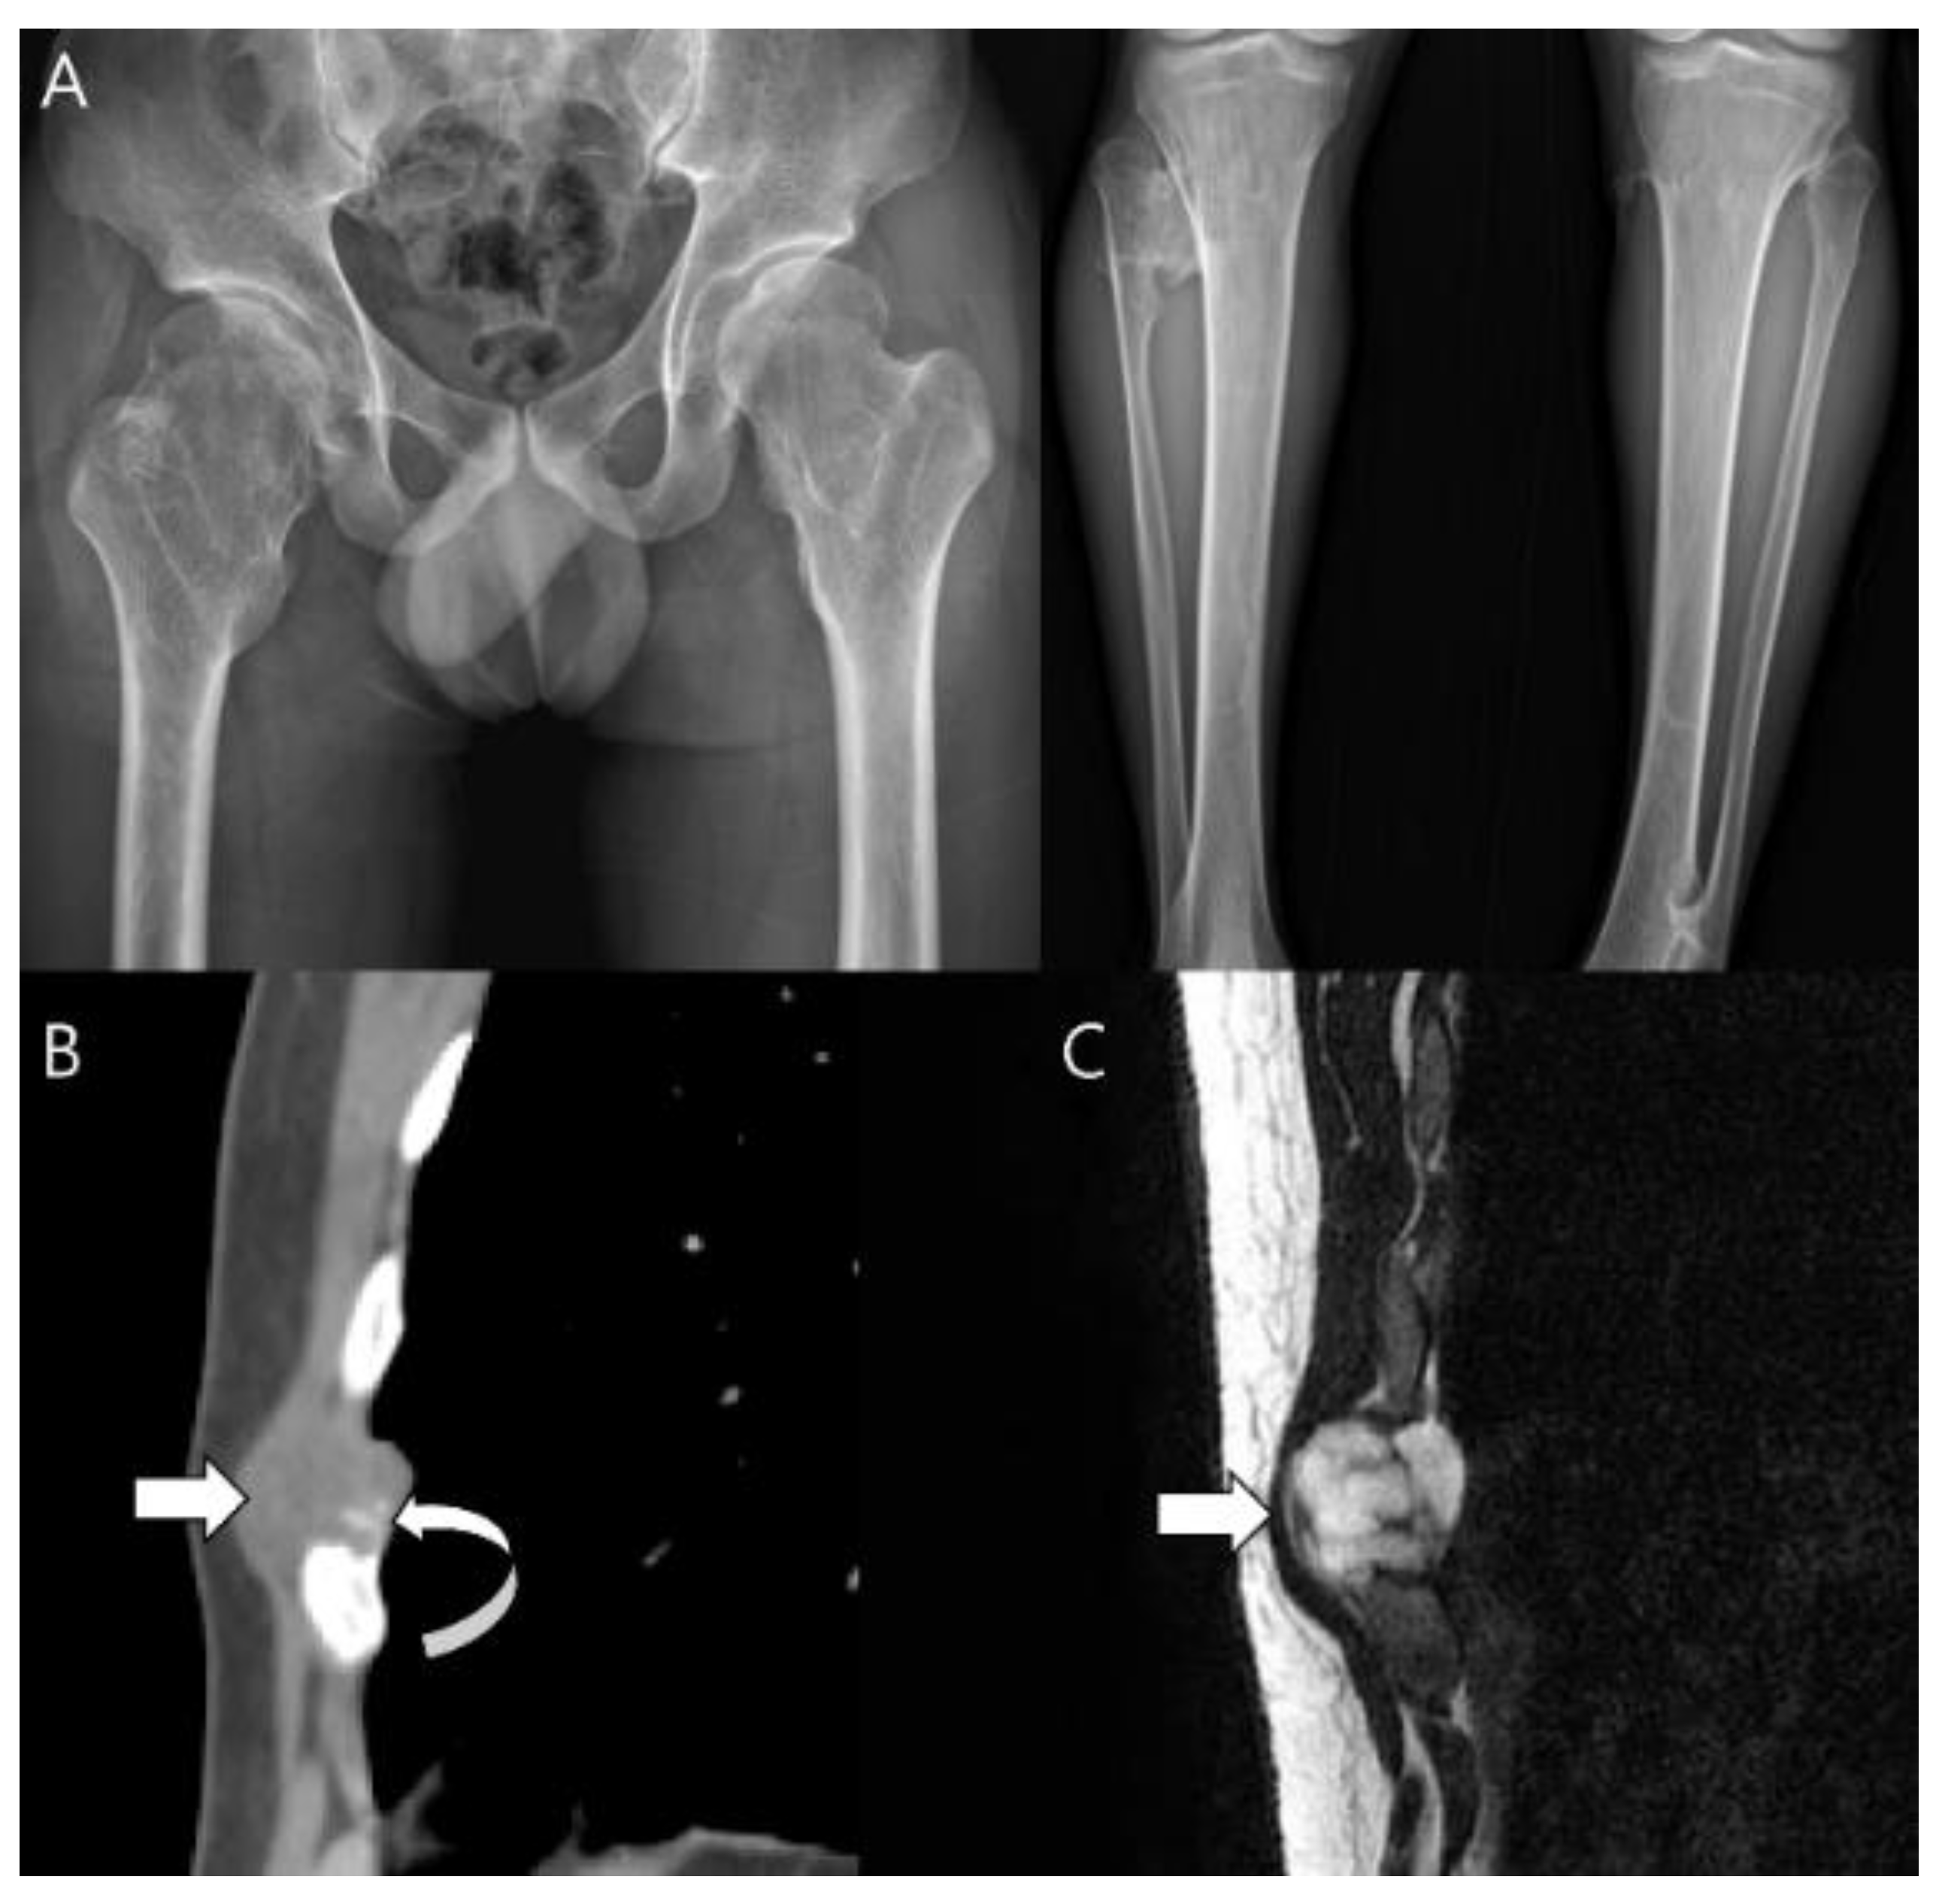

- Capanna, R.; Bertoni, F.; Bettelli, G.; Picci, P.; Bacchini, P.; Present, D.; Giunti, A.; Campanacci, M. Dedifferentiated chondrosarcoma. J. Bone Jt. Surg. Am. 1988, 70, 60–69. [Google Scholar] [CrossRef]

- Daly, P.J.; Sim, F.H.; Wold, L.E. Dedifferentiated chondrosarcoma of bone. Orthopedics 1989, 12, 763–767. [Google Scholar] [CrossRef] [PubMed]

- Mercuri, M.; Picci, P.; Campanacci, L.; Rulli, E. Dedifferentiated chondrosarcoma. Skelet. Radiol. 1995, 24, 409–416. [Google Scholar] [CrossRef]

- Grimer, R.J.; Gosheger, G.; Taminiau, A.; Biau, D.; Matejovsky, Z.; Kollender, Y.; San-Julian, M.; Gherlinzoni, F.; Ferrari, C. Dedifferentiated chondrosarcoma: Prognostic factors and outcome from a European group. Eur. J. Cancer 2007, 43, 2060–2065. [Google Scholar] [CrossRef]

- Littrell, L.A.; Wenger, D.E.; Wold, L.E.; Bertoni, F.; Unni, K.K.; White, L.; Kandel, R.; Sundaram, M. Radiographic, CT, and MR Imaging Features of Dedifferentiated Chondrosarcomas: A Retrospective Review of 174 De Novo Cases. Radiographics 2004, 24, 1397–1409. [Google Scholar] [CrossRef]

- Saifuddin, A.; Mann, B.; Mahroof, S.; Pringle, J.; Briggs, T.; Cannon, S. Dedifferentiated chondrosarcoma: Use of MRI to guide needle biopsy. Clin. Radiol. 2004, 59, 268–272. [Google Scholar] [CrossRef]